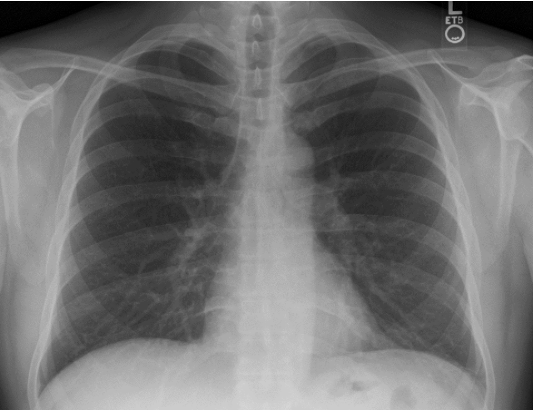

what ribs should you see on a chest xray?

-5-6 anterior ribs (in blue in pic)

-9 posterior ribs (purple)

what are the important anatomical landmarks to see on a chest x ray?

A

-manubrium

-diaphragm / liver

-heart - sup VC, aortic arch, atriums, inferior VC

-left main bronchus

-right main bronchus